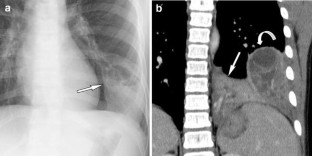

Fig. 1